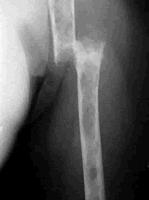

3、可有骨关节、腰背疼痛、颅骨、胸肋骨瘤形成,以胸肋、锁骨连接处发生串珠样结节及溶骨性钻凿样或鼠咬状圆形骨质缺损为特征,可出现病理性骨折、截瘫、肋间及坐骨神经痛等。

(4)骨骼X线检查可见多发性溶骨性穿凿样骨质缺损区或骨质疏松、病理性骨折。

1.骨痛、骨骼变形和病理骨折 骨髓瘤细胞分泌破骨细胞活性因子而激活破骨细胞,使骨质溶解、破坏,骨骼疼痛是最常见早期出现的症状,约占70%,多为腰骶、胸骨、肋骨疼痛。由于瘤细胞对骨质破坏,引起病理性骨折,可多处骨折同时存在。